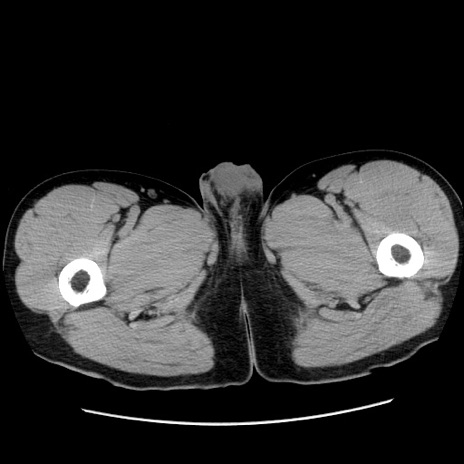

症例36(横断像)

【症例】20歳代 男性

【主訴】心窩部痛

【現病歴】今朝より上腹部痛あり。一旦軽快していたが再度出現したため救急要請。昨日夕に白身の魚を含む刺身を食べた。

【身体所見】BP 136/89mmHg、HR 74/min、BT 37.0℃、腹部:膨満、軟、心窩部に圧痛あり。反跳痛なし、筋性防御なし、腸雑音やや亢進あり。

【データ】WBC 17700、CRP 0.48

冠状断像